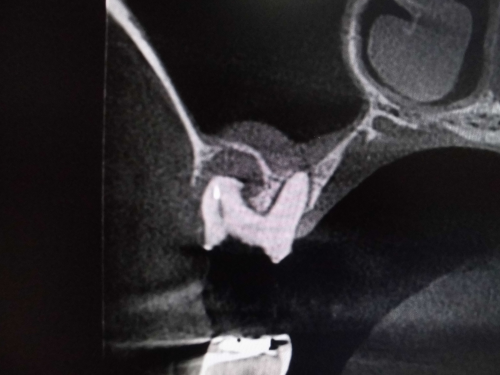

レントゲンでは不明な根尖病巣がCTでははっきり写ります。

同じ患者様です。根管が樋状根になっているのもわかります。